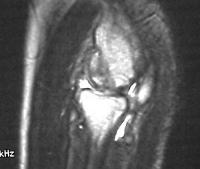

MRI shows an osteochondral sequestrum of the anterior capitellum:

Click for larger image